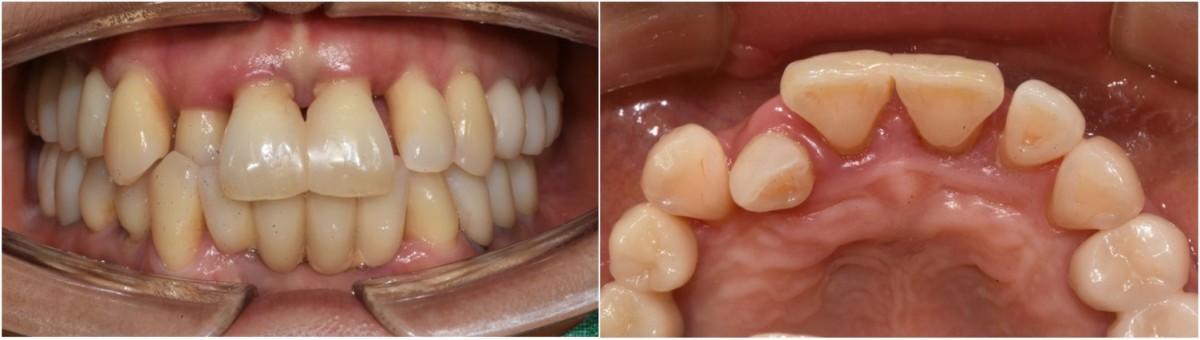

A 46-year-old female patient didn’t

have any systemic problems but a poor oral condition.

The patient is scheduled

for the implant and general prosthetic restoration in various parts. First of

all, the vertical stop is completed by several prostheses in the posterior

region, and the final stage of intraoral restoration is to proceed with an

anterior implant installation.